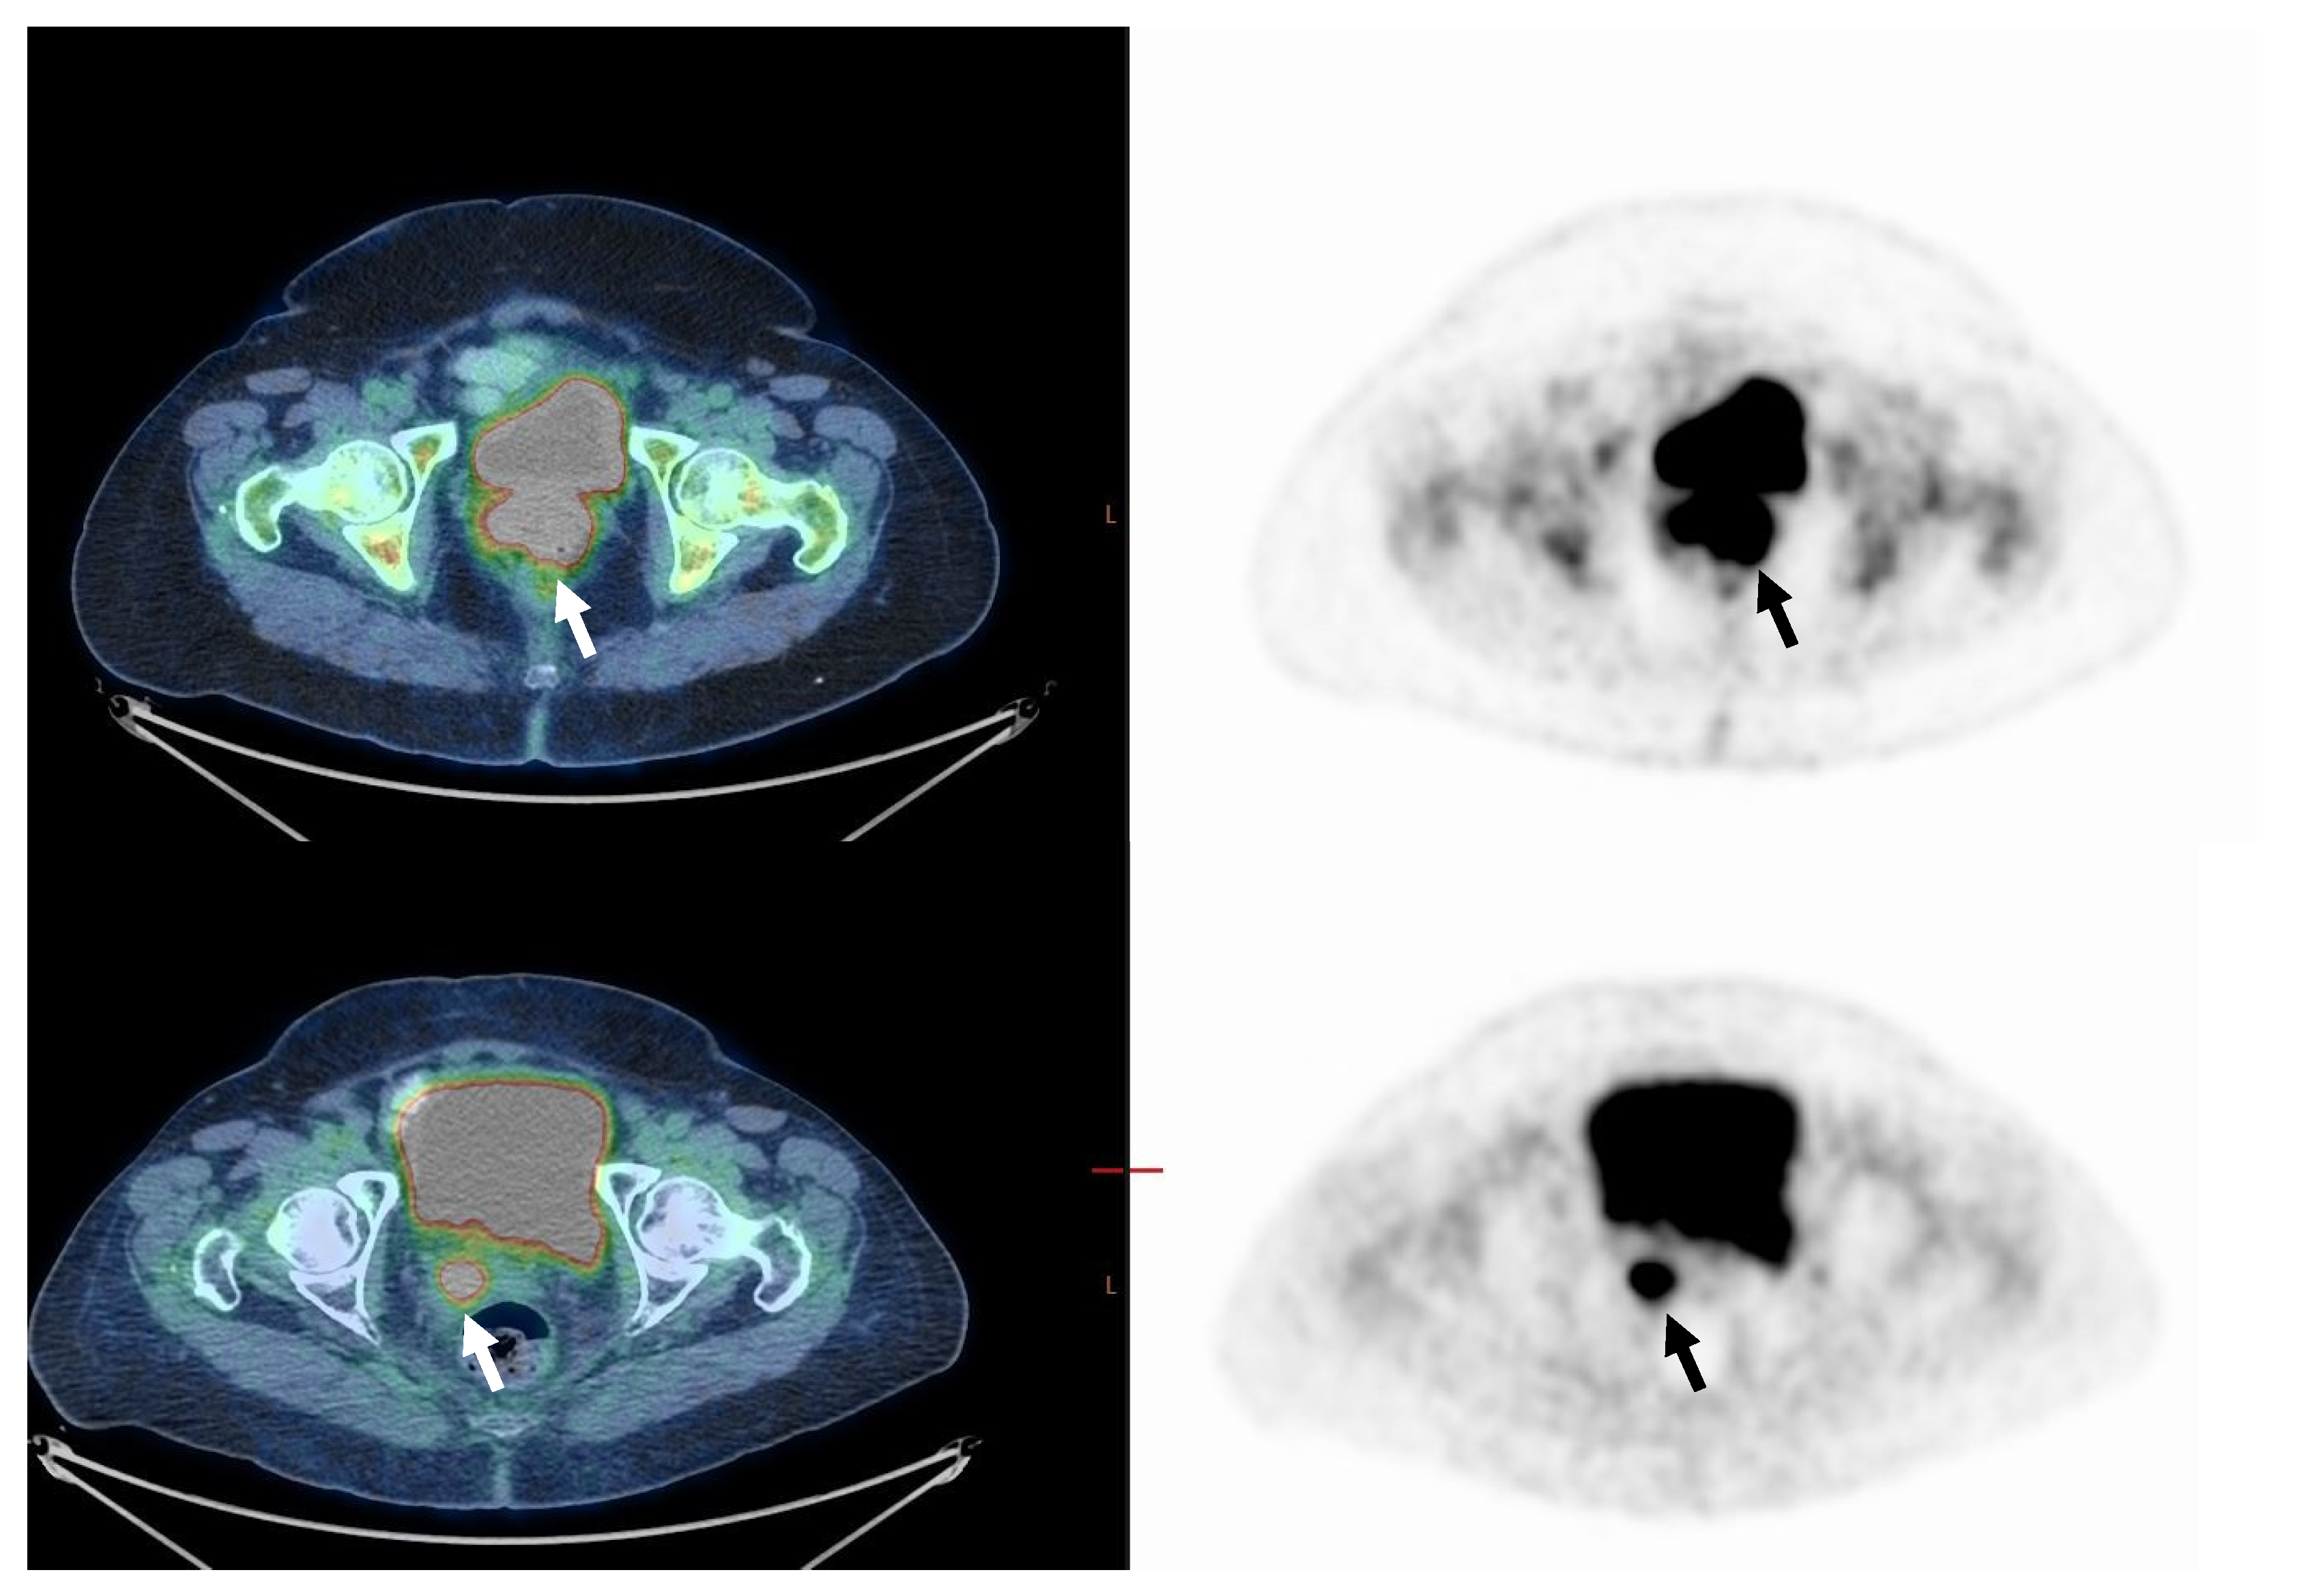

Figure 1. Sixty-two-year-old woman with FIGO stage IIB cervical cancer (Squamous cell carcinoma). On staging, PET/CT images (upper row) demonstrate uptake in the primary tumor only (arrow). MTV was 6.9 cm3 and TLG was 65.5. On PET/CT performed about 3 months after the end of treatment (lower row), no pathological uptake is seen (CMR, arrow).